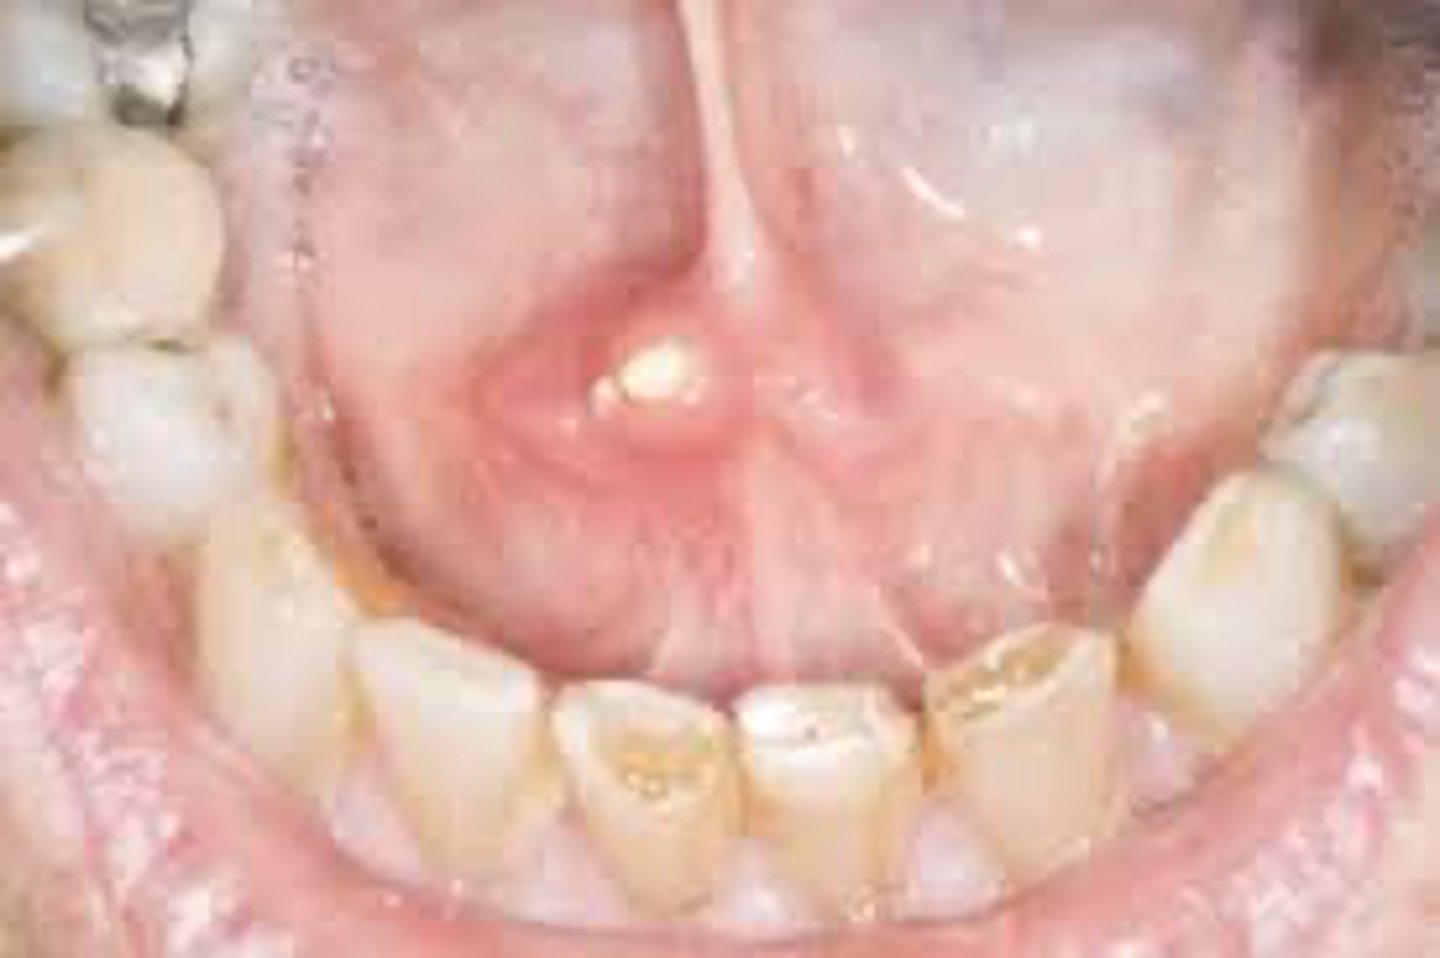

What is a painless, benign, dome-shaped, soft fluctuant nodule with a soft blue hue and some what translucent?

mucocele

Which location is MOST commonly associated with a mucocele?

lower lip

The most common cause of mucocele is:

trauma to minor salivary gland duct